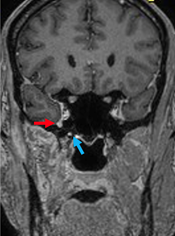

An 85-year-old male presented with a 6-month history of right hemifacial pain radiating to the ipsilateral ear, concomitantly with the onset of a skin lesion in the right malar region. He reported biopsy of a lesion in the same region 3 years ago, with local recurrence after 1 year, both resected with clear margins and a histopathological diagnosis of squamous cell carcinoma. MRI of the paranasal sinuses and brain showed a lesion consistent with tumor infiltration involving the infratemporal segment of the third branch of the right trigeminal nerve, extending to the foramen ovale and ipsilateral trigeminal cave, which was compressed (Figure 4) (Figure 5).

Figure 4 Magnetic resonance imaging, T1-weighted sequence with fat suppression. Coronal slices showing thickening and contrast enhancement in the right mandibular nerve (CN V3) at the level of the foramen ovale (blue arrow) and as it courses infratemporally within the masticator space (red arrow). The green arrow points to the normal contralateral foramen ovale for comparison purposes.

Figure 5 Magnetic resonance imaging, T1-weighted sequence with fat suppression. Axial slices showing anomalous contrast enhancement in the right foramen ovale (red arrow) when compared to the contralateral foramen (green arrow), consistent with involvement of the mandibular nerve (CN V3).